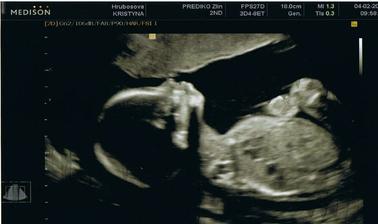

Naše miminko

Super fotecka z ultrazvuku;)Gratuluji k miminku

to jsou opravdu krásné vydařené fotky z UTZ 🙂